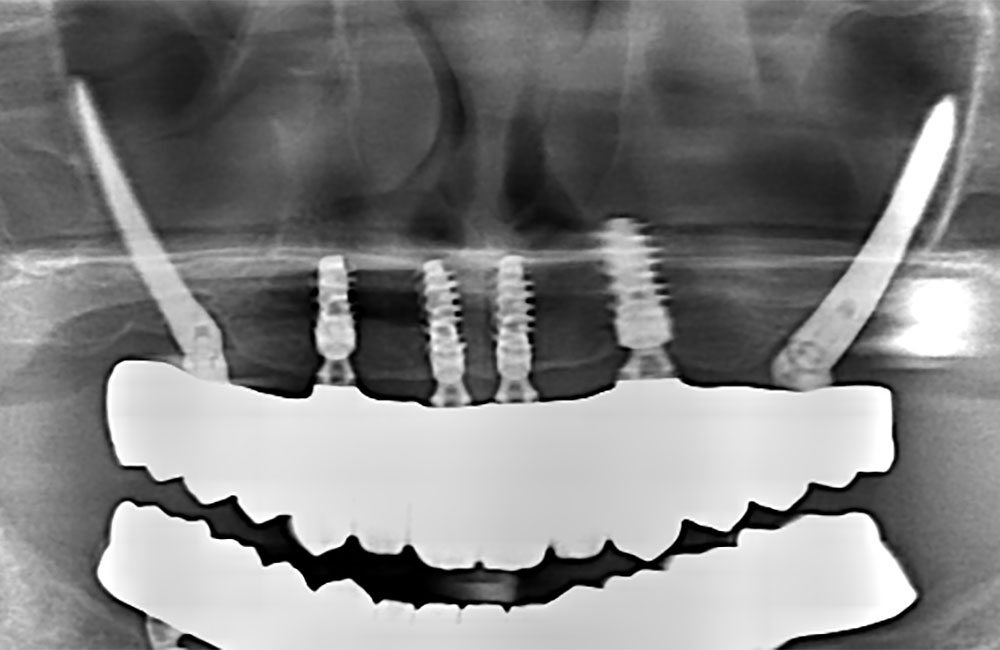

他院でザイゴマインプラント治療を受けた後、仮歯の噛み合わせが悪いため噛みづらく顔貌も変わってしまった。また頬に違和感を感じたため当院を受診。

術前のCT画像

左右のザイゴマインプラントが頬骨から大きく飛び出し頬を触ると違和感がある -

術後のCT画像

前方のインプラントは残し、他院埋入のザイゴマインプラントを除去し、同時に新しいザイゴマインプラントを適切な位置に再埋入を行っております。治療後数年経過しておりますが良好な状態を保っております。